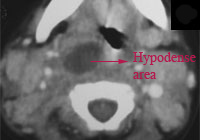

C.T. scan neck or MRI study of neck will also help in clinching the diagnosis. This must ideally be performed using intravenous contrast agents. It appears as a hypodense lesion in the retropharyngeal space with ring enhancement. Other effects that could be seen are soft tissue swelling, and obliteration of normal fat planes.

C.T. scan is really helpful in differentiating cellulitis from abscess.

Axial CT image of neck showing retropharyngeal abscess